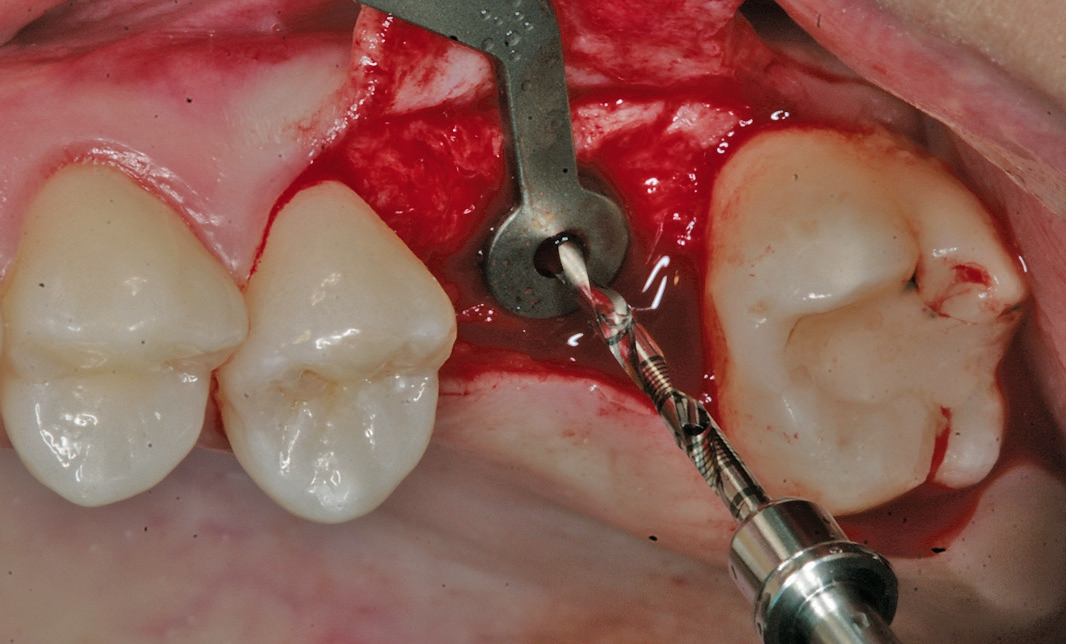

Eine der häufigsten Indikationen für Implantate überhaupt stellt die Einzelzahnlücke nach Verlust eines ersten Molaren dar. Bei den meisten Fällen liegt ein stabiles vertikales Knochenangebot an den Nachbarzähne vor, sodass in der Regel nach Ausheilung des apikalen Granulationsgewebes von einer guten Knochenregeneration auszugehen ist, so dass keine Notwendigkeit der Insertion von kurzen oder ultrakurzen Implantaten gegeben ist. Im Oberkiefer kann bei einer weiten Divergenz der Wurzeln des extrahierten Zahnes es zu einer ausgeprägten Pneumatisation der Kieferhöhle kommen. Daher werden gerade beim jugendlichen Patienten dort dann kurze Implantate eingesetzt, um auf eine Sinusbodenelevation mit einem lateralen Zugang verzichten zu können [3]. Die Implantate können mit oder ohne eine Navigationsschablone gesetzt werden [4]. Da die Lücke begrenzende Nachbarzähne eine gute Orientierung in der mesio-distalen Dimension ermöglichen, kann oftmals auch auf eine Orientierungsschablone verzichtet werden. In der oro-vestibulären Richtung muss der Anwendung des größeren Durchmessers Rechnung getragen werden. Dies kann mit einfachen Positionierungshilfen erfolgen, damit die Implantatachse möglichst zentral in der Kaufläche zu liegen kommt (Abb. 1-8). Die Einzelzahnlücke kann mit einer integrierten verschraubbaren Abutment-Hybrid-Krone oder mit einem Abutment und einer zementierten Krone versorgt werden [5].